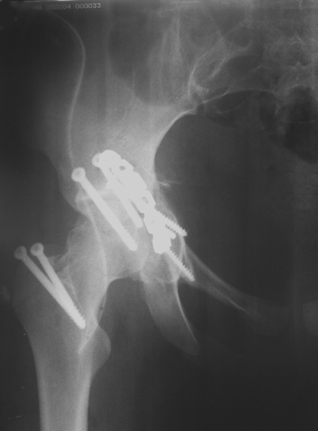

30/11/04 |  30/11/04 |  30/11/04 |  14/12/04 |  14/12/04 |  14/02/05 |  14/02/05 |  21/02/05 | Уважаемые коллеги! Случилось вторичное смещение вертлужной впадины после операции. Посоветуйте, что делать. Пациентка 18 лет. Травма 19.11.04. D.s.: Закрытыый Т-образный высокий перелом правой вертлужной впадины. Закрытый перелом м\мыщелкового возвышения левой б\берцовой кости. 9.12.04 операция - открытая репозиция, остеосинтез переломам вертлужной впадины. 30.12.05 выписаны на амбулаторное лечение с рекомендациями не вставать на правую ногу. 14.02.05 при контрольном осмотре на Р-граммах выявлено вторичное смещение передней колонны. Клинически подвывиха нет, имеется умеренная приводящая контрактура правого тазобедренного сустава, гипотрофия мышц н\конечностей. Госпитализирована в травмотделение. Выполнено КТ. Имеется смещение передней колонны кнутриЮ диастаз 8 мм. Посоветуйте пожалуйста, что предпринять в данной ситуации.

У больной имеется диастаз лонных и седалищных костей, то есть "разорвано" тазовое кольцо. В перспективе возможно образование ложного сустава на уровне основания лонной кости с болевым синдромом, поскольку седалищная кость не срастется.

2. ограничить двигательную активность до 6 мес. (не нагружать ногу, носить тазовый корсет-пояс и т.д.) с контролем сращения. Вроде бы на Р-граммах угадывается слабая тень формирующегося костного мостика по l. iliopectinea, это место в представленные срезы КТ не попало. Если к 6 мес. ничего не нарастет, то см. пункт 1.